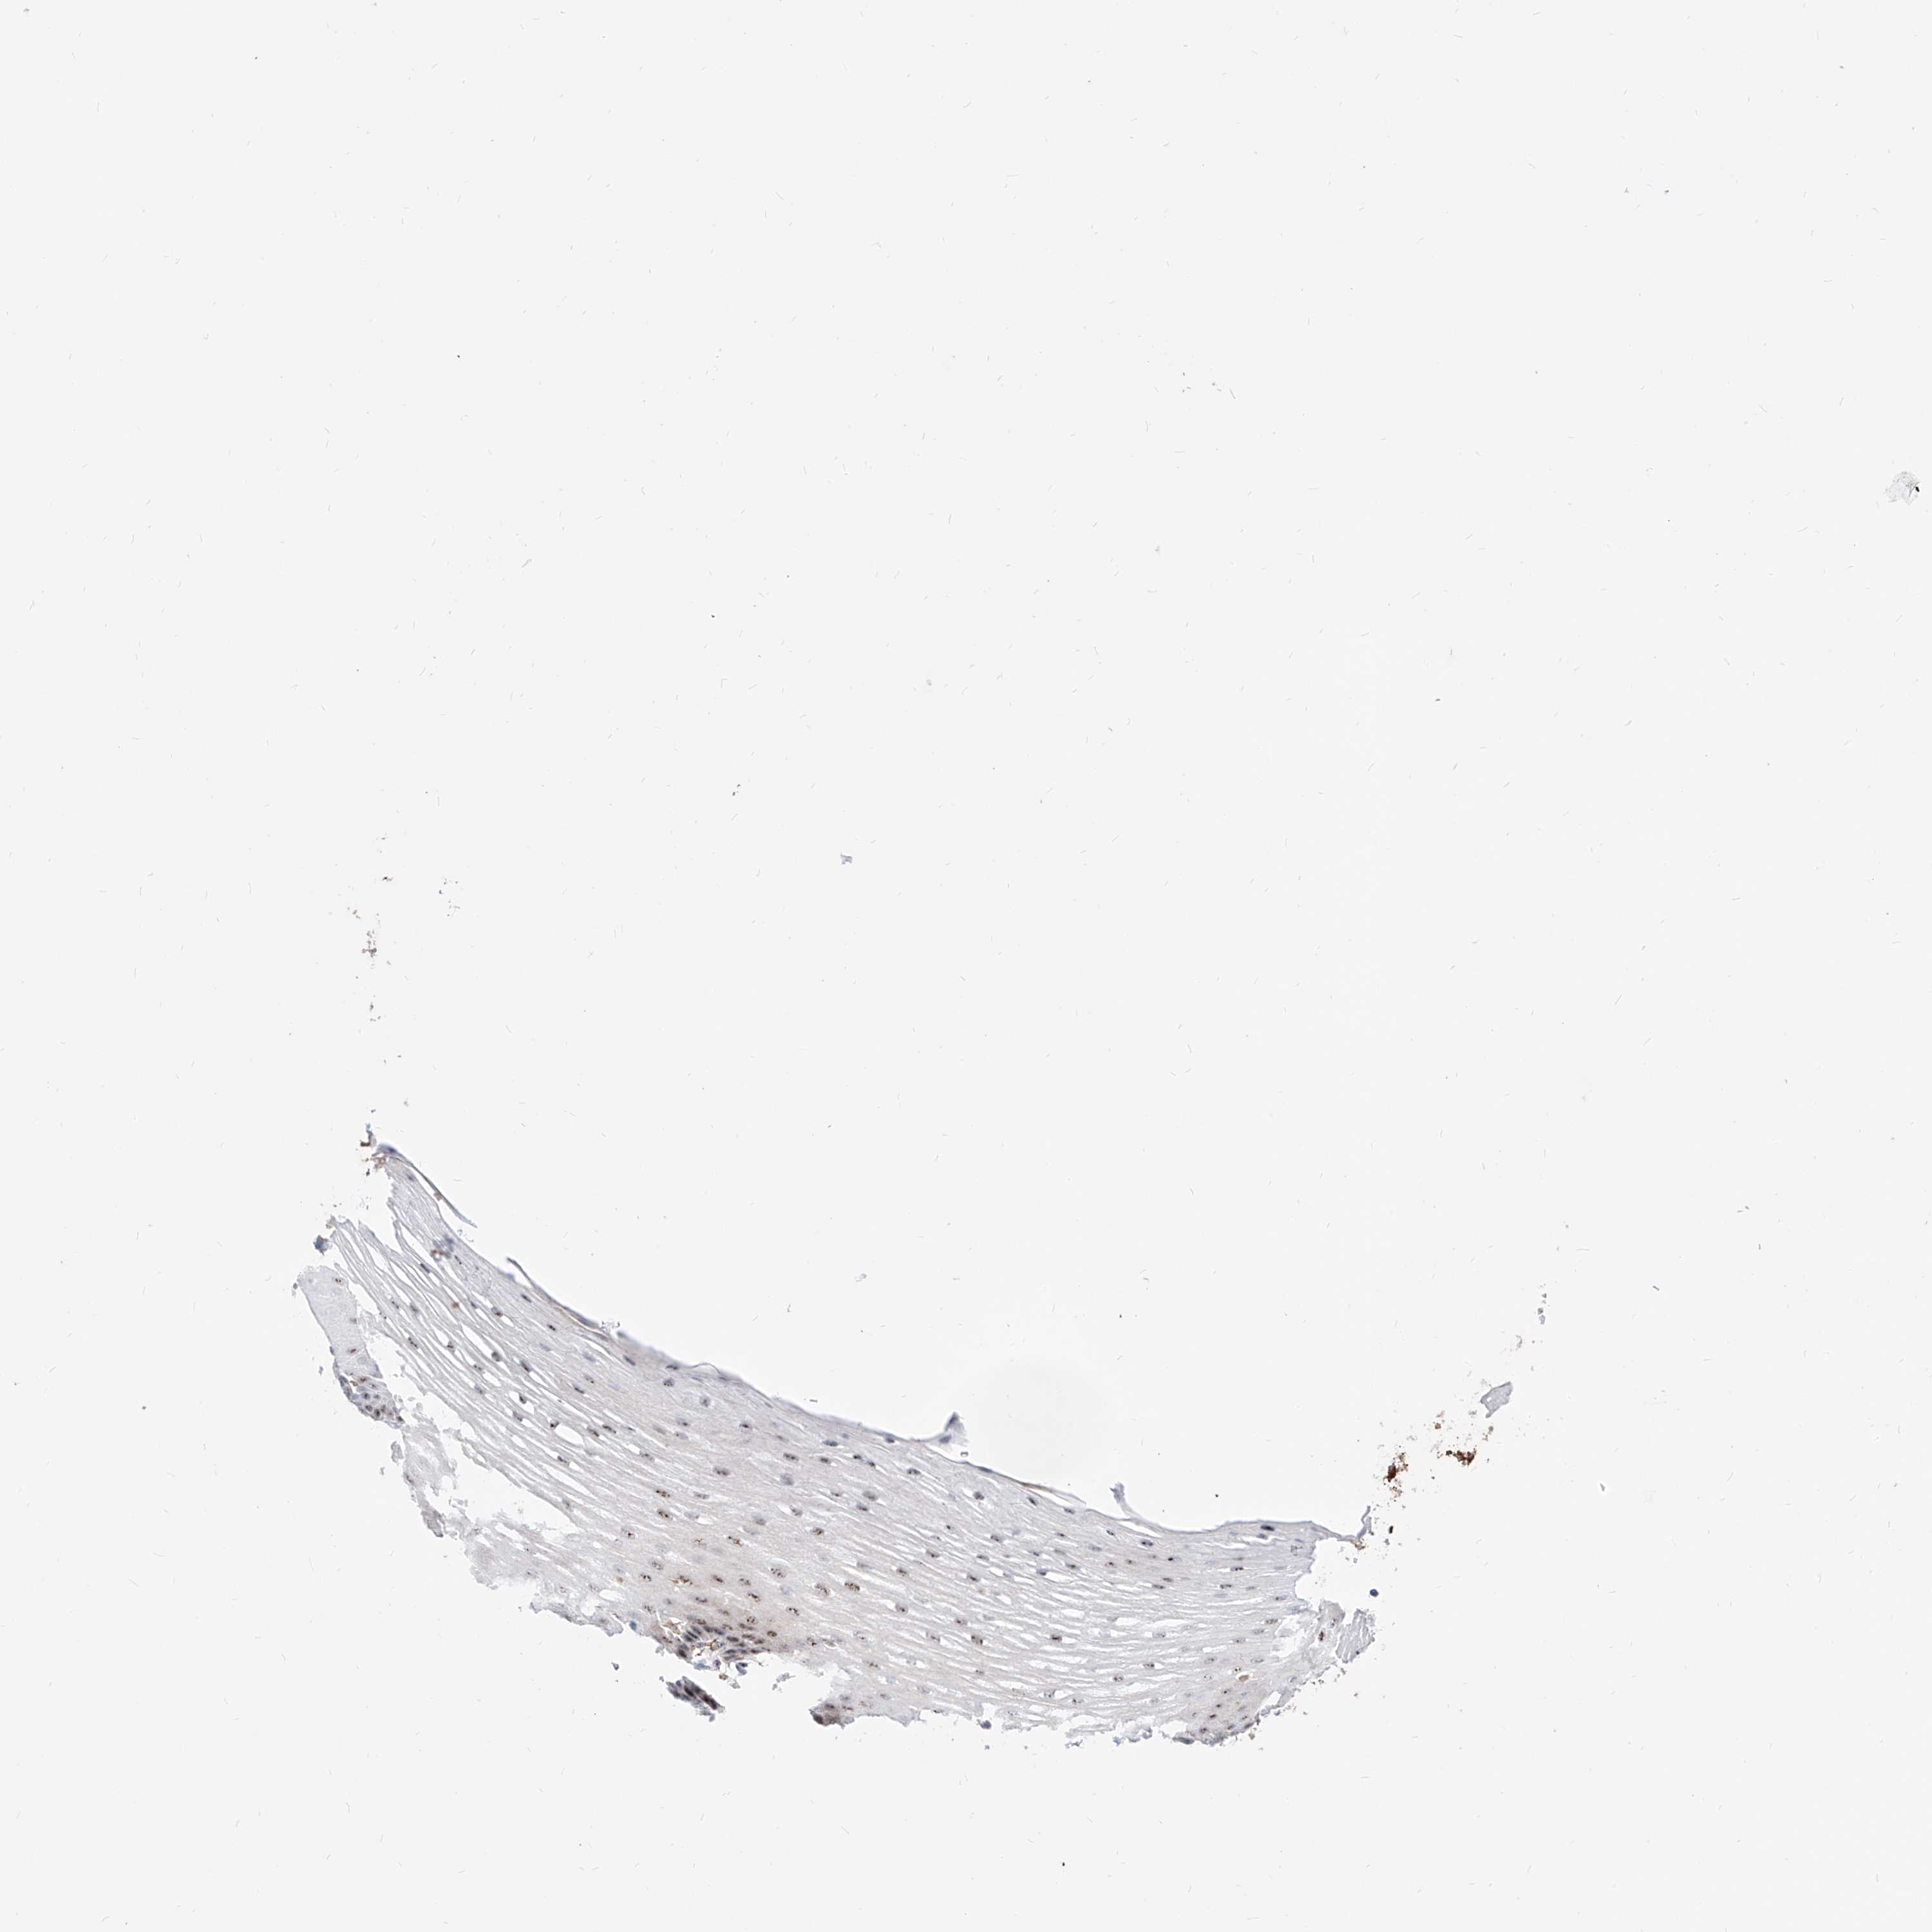

ESOPHAGUS - Antibody stainingi

Antibody staining in the annotated cell types in the current human tissue is reported as not detected, low, medium, or high, based on conventional immunohistochemistry profiling in selected tissues. This score is based on the combination of the staining intensity and fraction of stained cells.

Each image is clickable and will lead to virtual microscopy that enables deeper exploration of all samples and also displays staining intensity scores, fraction scores and subcellular localization as well as patient and tissue information for each sample.

Antibody CAB025557

Squamous epithelial cells Medium